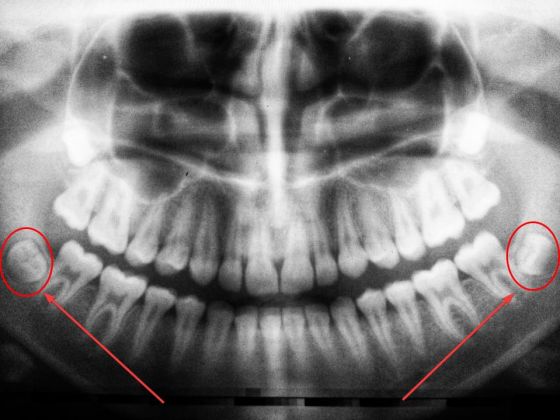

Во сколько лет начинают расти зубы мудрости?